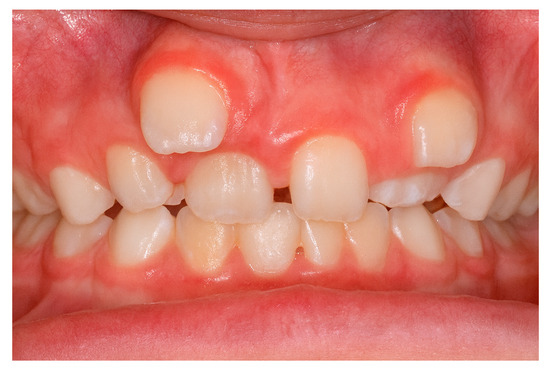

Background: Supernumerary teeth (ST) are developmental anomalies that may interfere with eruption, alignment, and occlusal balance. Their etiopathogenesis and management remain controversial. This multicentric study aimed to evaluate the epidemiological, morphological, and radiographic features of ST in a Romanian population and identify impact predictors. Methods: Between January 2020 and March 2025, 153 consecutive patients (91 males, 62 females; mean age 14.8 ± 6.2 years) with clinically and radiographically confirmed supernumerary teeth were evaluated across three Romanian academic centers: the University Dental Clinic, George Emil Palade University of Medicine, Târgu Mureș (n = 78 patients); the Department of Periodontology, Lucian Blaga University of Sibiu (n = 45 patients); and the Department of Dentistry, Dimitrie Cantemir University of Târgu Mureș (n = 30 patients). Results: A total of 185 ST were recorded, most frequently conical (48.6%) and mesiodens (56.2%). Complications were observed in 40.5% of patients. Multivariable analysis identified Angle Class III malocclusion (OR = 1.89; p = 0.039) and tuberculate morphology (OR = 2.93; p = 0.021) as the strongest independent predictors of impaction, alongside associations with younger age (<13 years) (OR = 3.12; p = 0.003) and male gender (OR = 1.78; p = 0.046). CBCT demonstrated high diagnostic concordance with OPG (κ = 0.89), but showed superior performance for complex cases, identifying 11 root resorptions and 9 vestibulo-palatal displacements that OPG missed. Multivariable analysis identified Angle Class III malocclusion (OR = 1.89; p = 0.039) and tuberculate morphology (OR = 2.93; p = 0.021) as the strongest independent predictors of impaction, alongside associations with younger age (<13 years) (OR = 3.12; p = 0.003) and male gender (OR = 1.78; p = 0.046). Conclusions: This multicentric study provides updated Romanian data and highlights novel risk factors and diagnostic selection guidelines that may support individualized treatment planning. Angle Class III malocclusion is a novel and critical independent predictor of supernumerary tooth impaction, alongside tuberculate morphology. This finding strengthens the rationale for utilizing CBCT specifically in Class III patients with ST to pre-emptively manage complex impactions and associated pathology. Full article

Figure 1